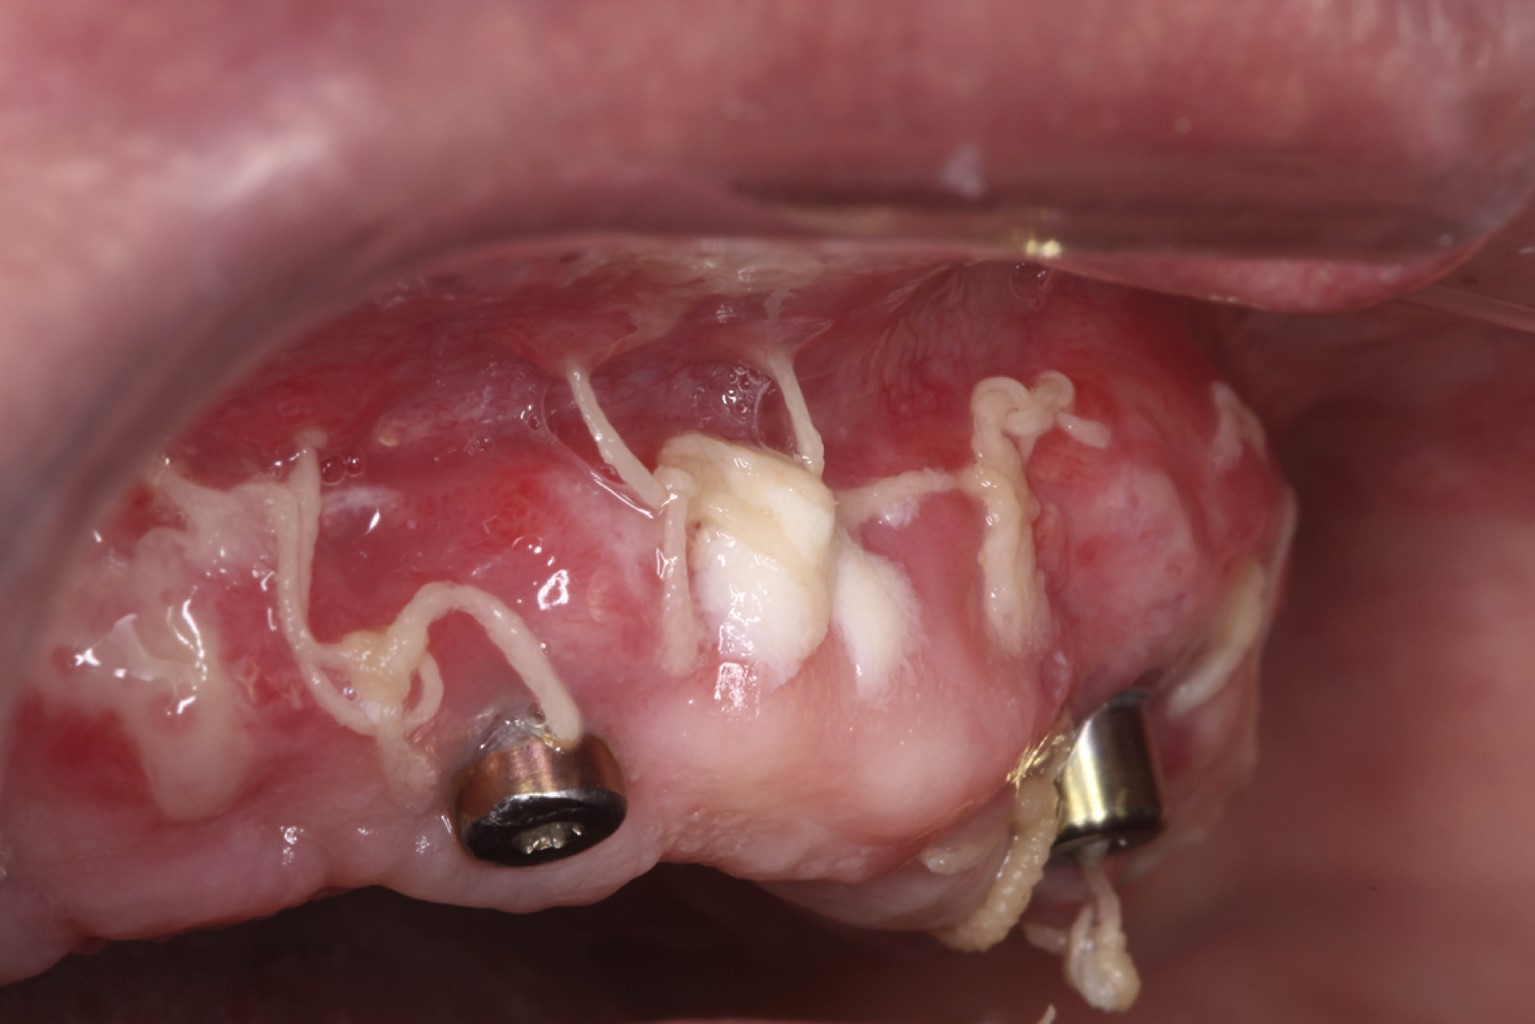

Manejo quirúrgico: después de aplicar el anestésico local apropiado (cloruro de articaína 4% con epinefrina 1: 100,000, Zeyco), la intervención quirúrgica comenzó con una incisión horizontal en el tejido queratinizado paralelo a la unión mucogingival sobre el reborde alveolar y tres incisiones de descarga perpendiculares a la primera incisión, dos en los extremos distales a la altura de la tuberosidad y una incisión en la línea media. Se elevó un colgajo de espesor parcial realizando disecciones en dirección apical con una hoja 15c manteniendo el bisturí casi paralelo al proceso alveolar, se posicionó el colgajo apicalmente y se aseguró al periostio con suturas de Vycril 4-0 creando una nueva línea mucogingival (Figura 2). Las fibras musculares y de tejido conectivo del sitio receptor se rasparon con un bisturí de Kirkland 15/16 para evitar la posterior movilidad del injerto dejando el lecho receptor como una cama de periostio. De forma simultánea se hidrató el injerto en solución fisiológica estéril durante 40 minutos como lo indica el fabricante. Una vez hidratado, se realizó la medición del sitio receptor y el aloinjerto fue cortado por la mitad creando dos injertos de 10 × 40 mm cada uno y colocados de forma individual en los sitios receptores. Para comprobar la orientación del injerto se colocó una gota de sangre del mismo paciente por cada lado tomando en cuenta que el Alloderm consta de un lado dérmico hidrofílico, que se puso en contacto con el periostio y el de membrana basal expuesto al medio bucal.

Figura 2